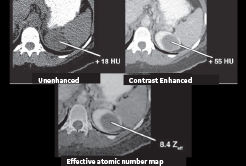

Effective-Z map

Effective-Z (effective atomic number) generated by GSI is accurate2 and closely related to diverse tissue electron density. Eff-Z map may help to illustrate tissue distribution. The accuracy of proton stopping-power ratio (SPR) prediction is dependent on the ability to correctly characterize patient tissues. Conventional CT HU-SPR conversion has limitations in dealing with human tissue diversity.1 Effective-Z map benefits for radiation oncology: Eff-Z may be used for prediction in proton therapy, with the potential1,3,4 to reduce uncertainties in particle range prediction5 and improve accuracy of dose planning.